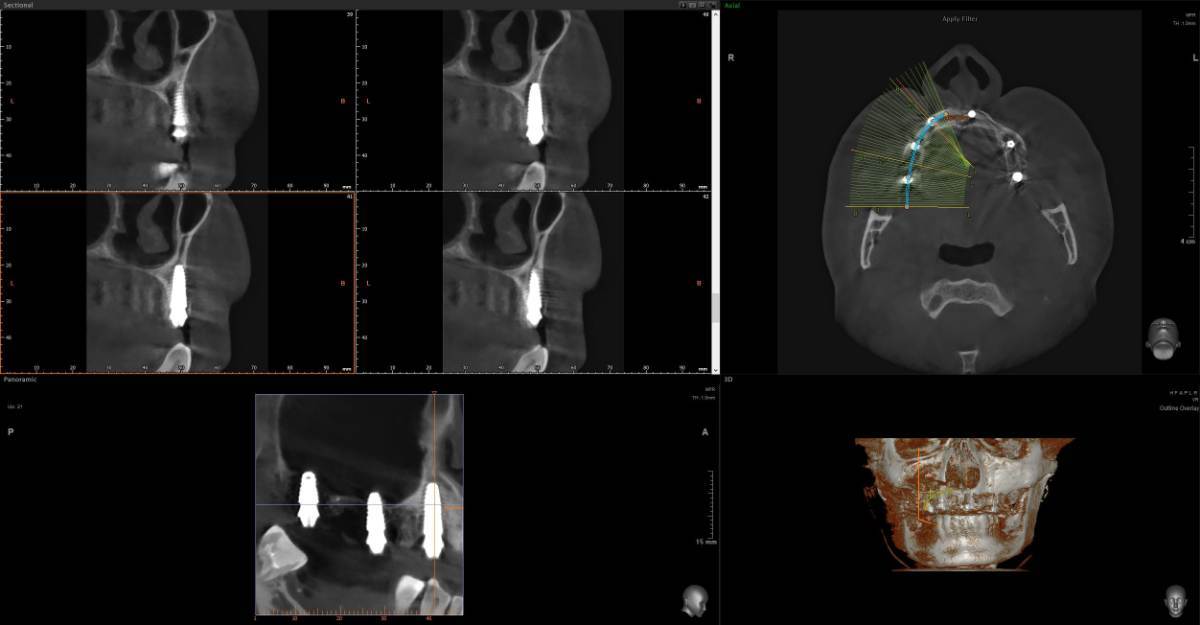

Добрый день. Зубы проблемные с детства очень сильно Полтора-два года назад предварительно удалось спасти не спасаемое, 26 и 27, по крайней мере по нескольких кт перидически, неплохой регресс и заживление костной ткани, даже в области 26 где было большое поражение фуркации, сейчас намного меньше, они не болят уже почти год, до этого очень долго болели даже после качественного лечения и врачи прогнозов не давали конечно же между 24-26 (25 нет уже лет 10) стоит адегизивный бабочка, уже не в самом лучшем состоянии, вернее зубы 24 26 не в очень хорошем, так вот я хотел снять бабочку и одеть на 24-26 металлокерамику, во рту есть несколько металлокерамик единичных, на 3 еще не ставил Есть вариант, и я послушал разных докторов, что можно было бы например 24 просто сделать реставрацию качественно, 26 там без вариантов покрыть коронкой единичной, а 25 имплантат, но я пока избегаю всего так сказать инвазивного, хотя бы еще полтора-два года, с начала 2024 и по середину 2025 болел очень тяжело, Лонг ковидом, это страшное явление которое врагу не пожелаю, возможно даже кто помнит мои темы что я у себя предполагал сепсис, вот именно у меня был он не в виде усталости какой и тд, что чаще всего, а в форме выраженного иммунодефицита + легкого но стойкого системного воспаления , по типу аутоиммунных реакций, в общем не будем вдаваться в эту тему, к тому же она не изучена еще, все только предстоит, спасибо лишь тем докторам-интузиастам, которые просто из спортивного интереса не забросили эту тему и занимаются исследованиями, при разных НИИ, в итоге они меня спасли, помогли определенные противовирусные на длительной основе поставить меня на ноги, что еще раз и том числе мой пример подтверждает вирусный генез Лонга, 1,5 жизни просто выпало у меня Ладно, я далеко ушел уже от темы, я к тому, что более современно наверное считается имплантат и 24 и 26 по отдельности, но повторюсь я боюсь пока лишних инвазивных процедур. Подскажите пожалуйста, каковы минусы моста с металлокерамики на 3 зуба, по каким причинам это считается прошлый век, и какие нюансы меня могут ждать ? Даже если те зубы я рано или поздно потеряю, но даже 3-4 года выиграть еще перед имплантацией, это все равно выигрыш Возможно я думал тот же мост на 3 но из циркония, но тоже не знаю, зубы те хоть и с положительной динамикой но сколько они еще простоят, а цирконий как никак в 2 раза дороже металлокерамики, но если лучше его, тогда рассмотрю -